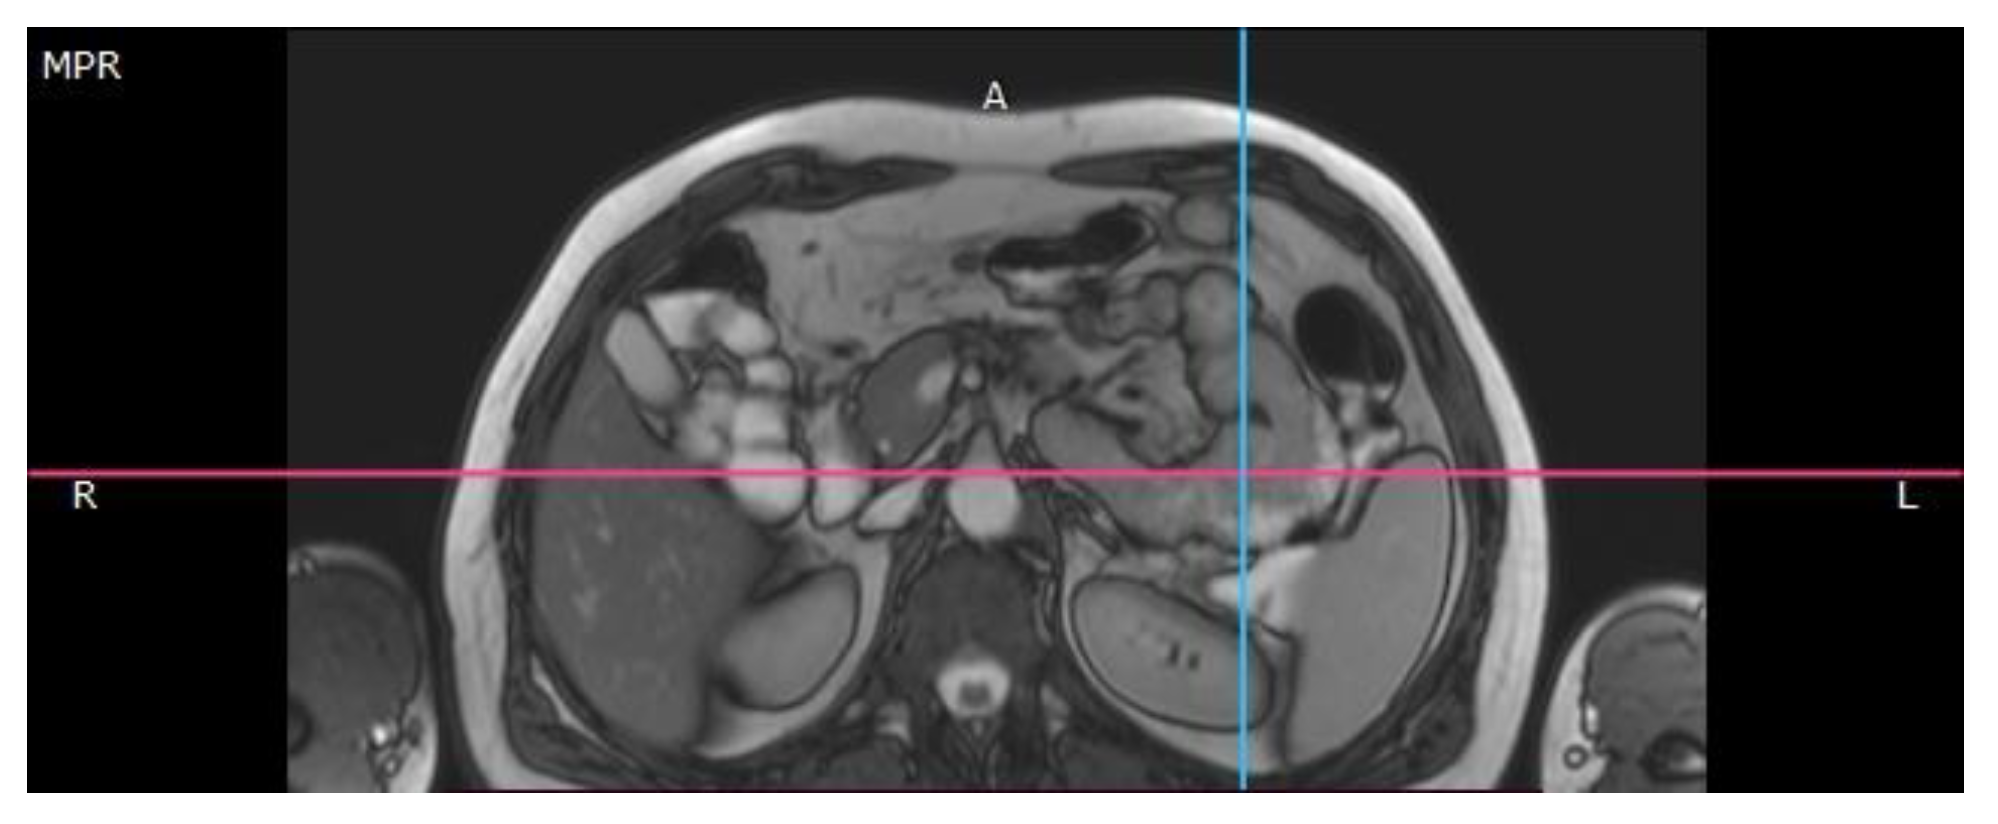

Case Presentation